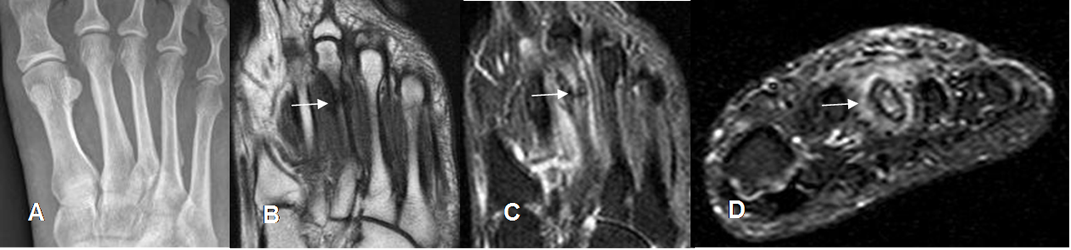

A: Rx AP. No se encuentran alteraciones.

B: RM Coronal en T1, C: RM coronal en STIR y D: RM axial en STIR. Fractura no desplazada y con formación de callo óseo, en la unión entre el tercio medio y distal del 3º metatarsiano, con cambios inflamatorios en los tejidos blandos.